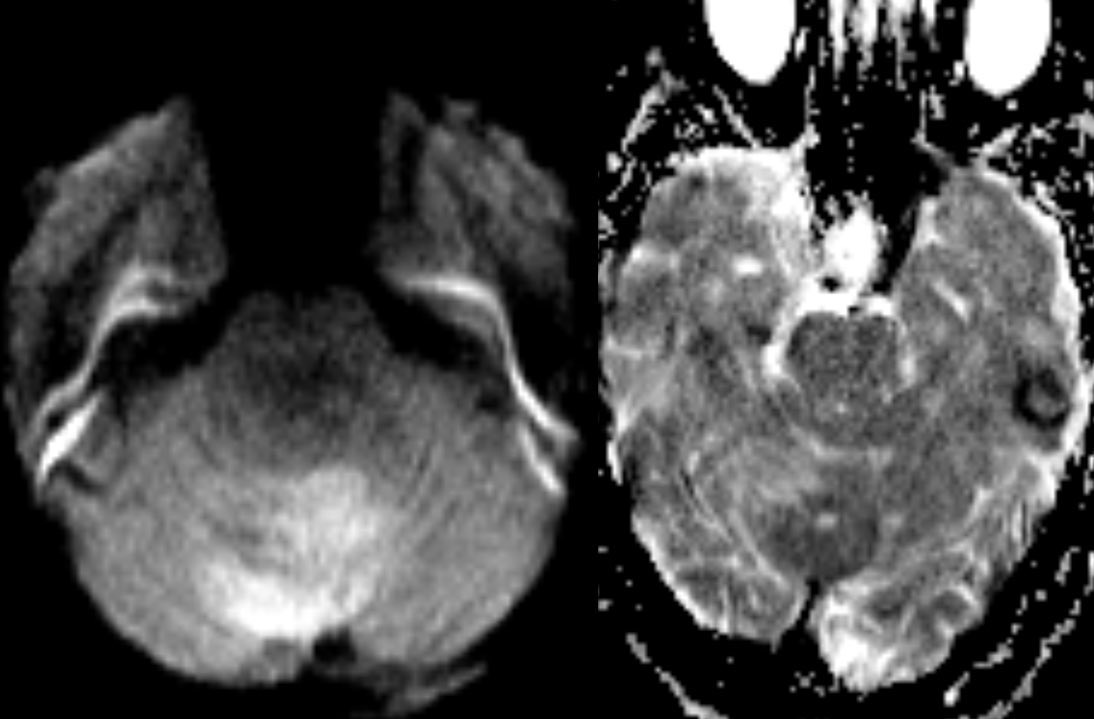

🔷Imaging:

💡 Hypercellular tumor so DENSE on CT and DIFFUSION RESTRICTION (consistent feature)

▶️Round/lobulated morphology

▶️Hemorrhage is rare but calcifications seen in ~20%

💡 Most medulloblastomas enhance except group 4 which may have minimal to no enhancement

⭐️ Companion case of Lhermitte-Duclos - Unilateral cerebellar mass w/ striations due to hyperintense expanded fovea on T2 w/ normal signal intervening parenchyma

Typically there is no to little enhancement and high signal on DWI due to T2 shine-through w/ high signal on ADC x.com

💡 Both Lhermitte-Duclos & Medulloblastoma SHH can have a striated appearance! Use DWI/ADC, density on CT, & enhancement to distinguish!